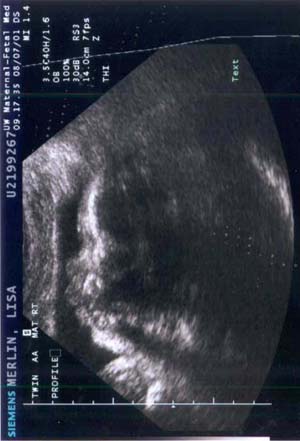

Baby A during ultrasound on 7 AUG 2001 - Week

34

The profile of the head facing left.